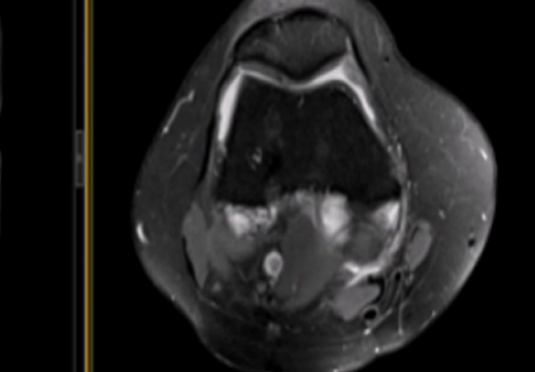

針對腫瘤術后患者,涵蓋手術、放療、化療后康復期管理。

微創射頻消融術

適用于微創射頻熱消融術治療患者,引進權威醫療團體輔助引流。